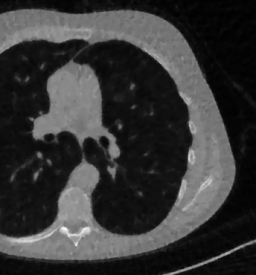

The considered images are pixel reconstructions of human abdomen, computed from full-dose acquisitions. In Figure 2 we depict one image with two zooms-in highlighting areas with different anatomical structures, such as pulmonary details, sections of ribs and low-contrast inter-costal muscles.

In all the experiments reported in 5.1, we have used the images from the data set as ground truth references.

Here we present the results of RISING applied to the Mayo data set introduced in paragraph 4.1. As previously mentioned, we consider two sparse-view CT geometries, namely and . In Figure 4 we report the results for the protocol, achieved on one image of our test set. The top-left image represents the reconstruction. Even if only a small number of iterations are performed, the main structures of the abdomen are visible; however, the image is still blurry. In the image, shown in the upper-right corner, we notice that the TV regularizer has acted to totally eliminate the artifacts and noise, improving the uniformity of the image in the inner structures. When compared to the ground-truth solution in Figure 2, the contours of the details in appear slightly jagged, differently from where they are neat but, usually, corrupted by artifacts. The bottom row of Figure 4 shows the two and images, respectively from left to right. It is evident that has retrieved many details but it presents noisy components, reflecting the features of its target image . Our solution is less corrupted, since the low-contrast regions are correctly preserved and the noise is not visible. These observations are confirmed by Figure 5, which plots the intensity profiles taken over the red line in the second crop (Figure 2). In our approach (on the right) the CNN has accurately learnt the map of (8) and the red profile mostly overlaps the black one. On the contrary, the profile (on the left) is more distant from its target reference.